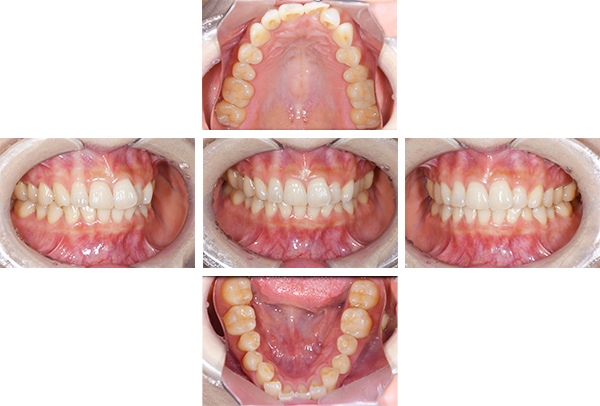

歯列矯正・インレー・クラウン症例

前歯が黒っぽいのが気になる、

悪いところは全部治したい

年齢 54代女性

主訴 歯をきれいにしたい

治療

期間

4年

費用 セラミックインレー 12本

660,000円

オールセラミックプレミアムクラウン 3本

495,000円

矯正 874,900円

計 2,029,900円(税込)

※全て税込となります。

症例写真(治療前)

担当医師所見

治療前:

八重歯が目立ちます。また銀歯もおおく、見た目が気になります。虫歯も散見できます。

症例写真(治療後)

治療後:

矯正治療と虫歯の治療すべて終わったときの写真になります。見た目も最初の頃とは全く違いますし、お口の中もすごく綺麗です。

方針

まずは虫歯の治療を行い、被せ物をする部分は仮歯をいれて矯正を行う。矯正終了後、仮歯の部分を最終的な被せ物に変えていく。また気になっていた銀歯もセラミックに変えて終了となった。

内容

セラミックインレー、オールセラミックプレミアム、矯正

特記

事項

虫歯の治療によって歯が一時的に染みるようになる可能性があります。また、歯を抜かずに矯正を行っていますが、全ての方で歯を抜かずに矯正ができるわけではありません。

治療リスク・副作用

・詰め物を銀歯からセラミック等のインレーに変えると、歯がしみることがある

・被せ物をやりかえる時は中で大きく虫歯になっていたり、歯が割れている場合は抜歯になることもある

・インプラント治療は骨と結合するのに期間がかかるが、個人差がある

・ホワイトニング後は歯がしみることがある

・詰め物、被せ物をする時は自分の歯を削ることになります